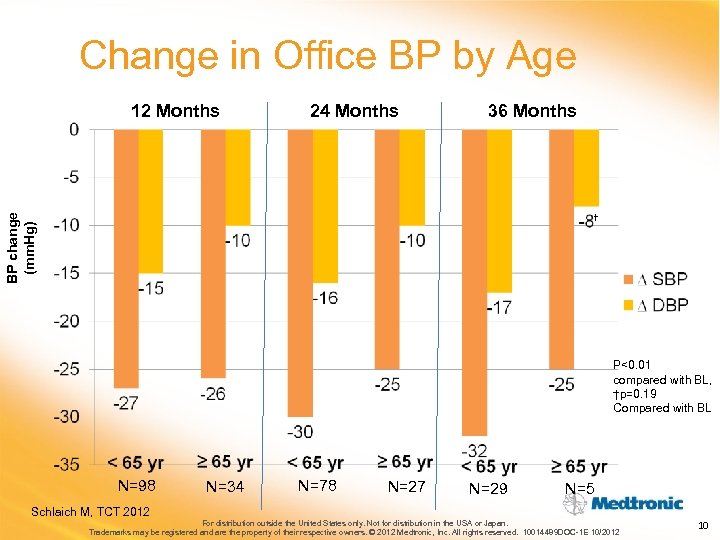

Change in Office BP by Age 12 Months 24 Months 36 Months BP change (mm. Hg) † P<0. 01 compared with BL, †p=0. 19 Compared with BL N=98 Schlaich M, TCT 2012 N=34 N=78 N=27 N=29 N=5 For distribution outside the United States only. Not for distribution in the USA or Japan. Trademarks may be registered and are the property of their respective owners. © 2012 Medtronic, Inc. All rights reserved. 10014489 DOC-1 E 10/2012 10

Change in Office BP by Age 12 Months 24 Months 36 Months BP change (mm. Hg) † P<0. 01 compared with BL, †p=0. 19 Compared with BL N=98 Schlaich M, TCT 2012 N=34 N=78 N=27 N=29 N=5 For distribution outside the United States only. Not for distribution in the USA or Japan. Trademarks may be registered and are the property of their respective owners. © 2012 Medtronic, Inc. All rights reserved. 10014489 DOC-1 E 10/2012 10